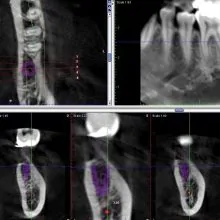

当院では事前にCTを撮影し、インプラントのシミュレーションをして治療を行なっております。

CT上で神経との距離を測ることにより術後の神経の損傷するリスクを下げることができます。